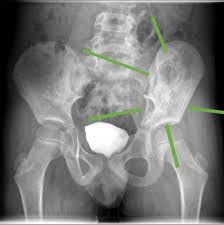

سرطان الحوض إستشاري

أعراض التهاب عظام الحوض سطور